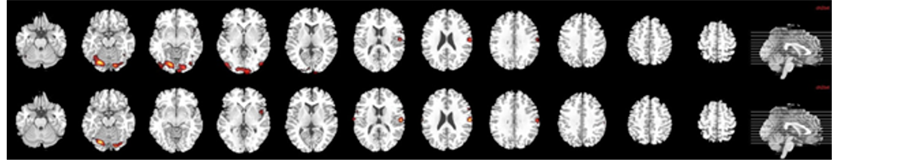

During the processing of neutral faces compared with baseline (12 foci), there was a significant activation in the following brain areas: temporal areas (left superior and middle temporal gyrus), visual areas (left calcarine, left lingual gyrus, left lateral occipitotemporal gyrus) and left pre- and postcentral gyri (cluster-level Familywise Error Rate FWE correction (p < 0.05); Table 2, Figure 2(a)).

Figure 2. Brain map of neural activation in response to both neutral (a) and 100% fearful facial (b) expressions compared with fixation cross in B.D. in acute stroke before and after rehabilitation program.

2.2.2. Processing 100% Fearful Faces

The response to fearful stimuli recruited the following areas with significantly increased BOLD signal (9 foci): visual areas (left calcarine, left lingual gyrus, left fusiform gyrus), left pre and postcentral gyri and right cerebellum (cluster-level FWE correction (p < 0.05); Table 2, Figure 2(b)).

The processing of neutral faces compared with baseline (8 foci) showed increased neural activation in the following regions: visual areas (left lingual gyrus, left fusiform gyrus), left precentral and right postcentral gyri and right cerebellum (cluster-level FWE correction (p < 0.05); Table 2, Figure 2(a)).

2.3.2. Processing Fearful Faces

After therapy of B.D., significantly increased brain activation was reported in the following brain areas (4 foci): bilateral postcentral gyrus, right cerebellum and left lingual gyrus (cluster-level FWE correction (p < 0.05); Table 2, Figure 2(b)).

Hence, before therapy of B.D. recruitment was larger in the left hemisphere, both with neutral and fearful faces.

In response to neutral faces, visual cortex was significantly activated including calcarine and fusiform gyrus. Before treatment was provided, perception of 100% fearful expressions recruited cerebellum, precentral gyrus and visual regions but not amygdala.

B.D. showed fewer post-therapy activation maps compared with pretherapy ones and more significantly activated pre- and postcentral gyrus and right cerebellum in response to 100% fearful faces.

Interestingly, neither amygdala nor visual areas including fusiform gyrus and calcarine were activated as the response to fearful stimuli after therapy completed.